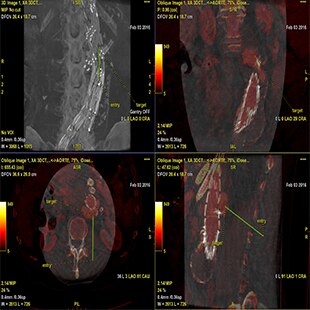

Planifier

Guider

Évaluer